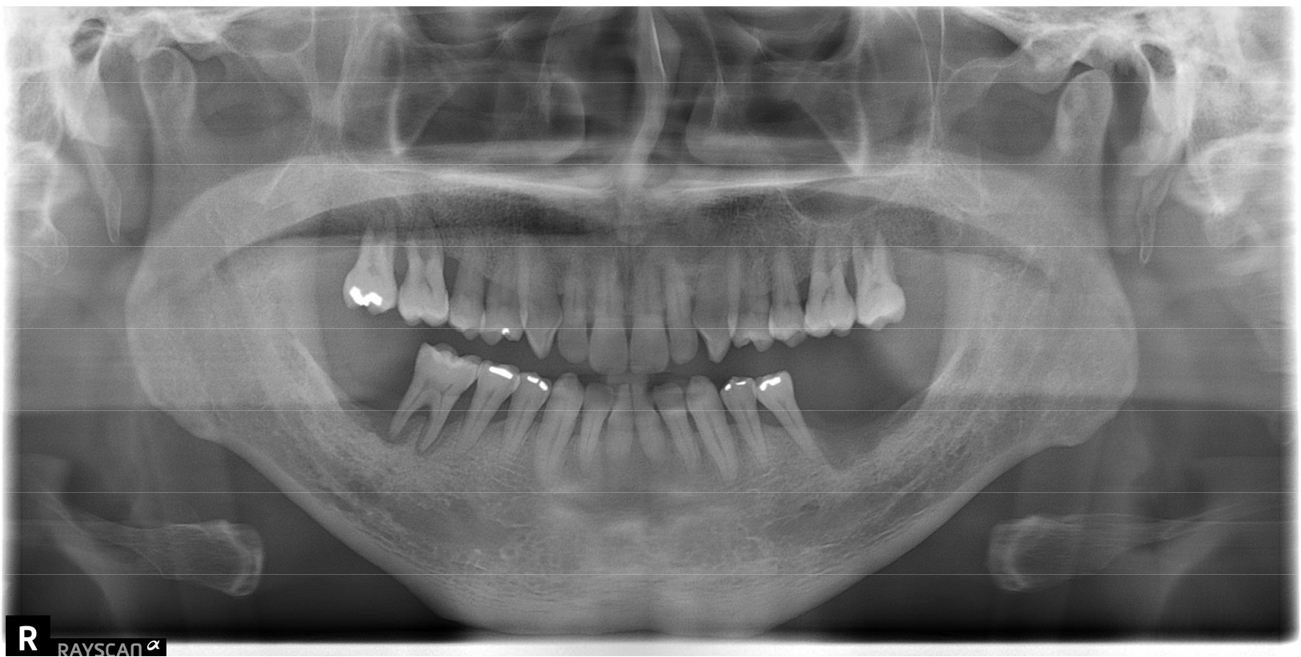

A 64-year-old man was referred for rehabilitation with dental implants in the partially edentulous lower jaw. The patient had no relevant medical history. On oral examination, the patient demonstrated severe alveolar bone resorption and tooth loss, particularly in the lower posterior area (Fig. 2). Among the rehabilitation options, the patient decided to extract a hopeless tooth and implant placement.